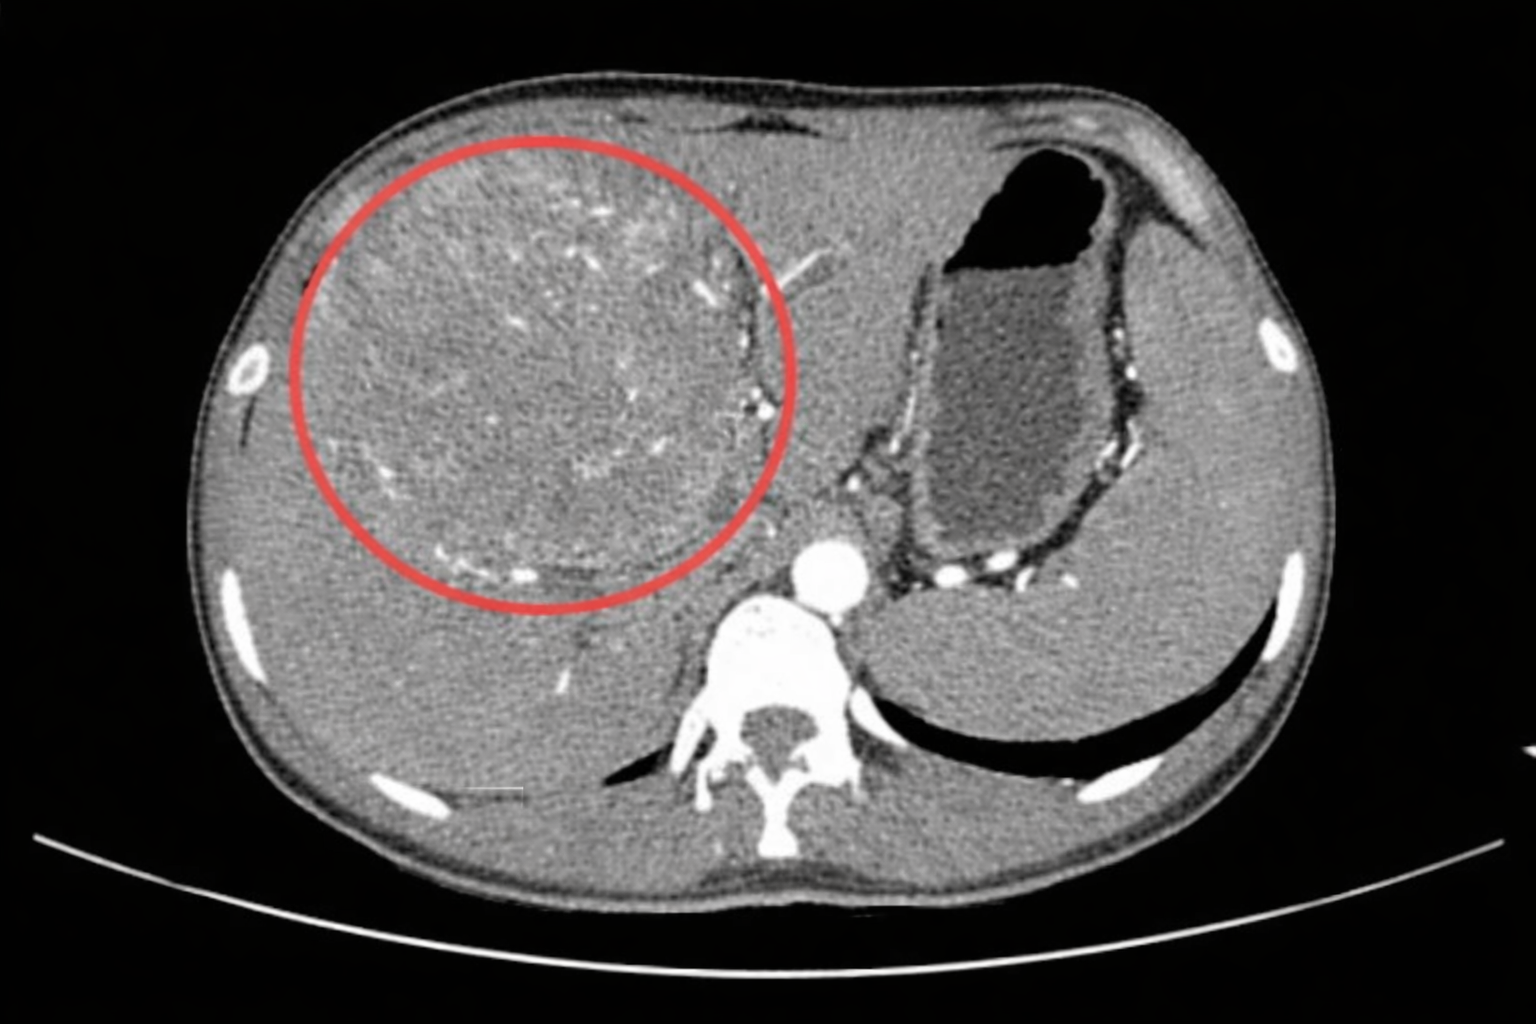

Bệnh nhân là một nam thanh niên 25 tuổi, trên phim chụp cắt lớp vi tính (CT) xuất hiện dòng chữ lạnh lùng: “Khối u gan kích thước lớn”, kèm chẩn đoán ung thư gan giai đoạn cuối.

Mới đây, Bệnh viện Trung tâm Vịnh Binhai, thành phố Đông Quan, Trung Quốc đã tiếp nhận một ca bệnh khiến nhiều người không khỏi bàng hoàng. Bệnh nhân là một nam thanh niên 25 tuổi (tên đã được thay đổi), trên phim chụp cắt lớp vi tính (CT) xuất hiện dòng chữ lạnh lùng: “Khối u gan kích thước lớn”, kèm chẩn đoán ung thư gan giai đoạn cuối.